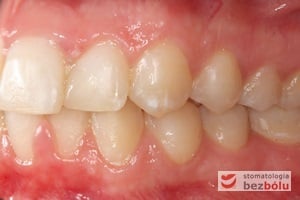

Pacjentka lat 22 zgłosiła się do naszej placówki celem podjęcia leczenia ortodontycznego. Głównym oczekiwaniem pacjentki była poprawa estetyki uśmiechu oraz brak ekstrakcji zębów na drodze do jej uzyskania. Ze względu na liczne stłoczenia zębów w górnym i dolnym łuku, dość duży materiał zębowy w porównaniu z bazą kostną, a także zgryz przewieszony boczny prawostronny po dokładnej analizie cefalometrycznej oraz analizie modeli diagnostycznych zastosowano leczenie bezekstrakcyjne z wykorzystaniem strippingu jako alternatywy dla usuwania zębów, mającego na celu uzyskanie miejsca w łuku na uszeregowanie zębów. Po fazie aktywnego leczenia trwającego 18 miesięcy zastosowano leczenie retencyjne w postaci szyny retencyjnej w łuku górnym oraz retainera stałego w łuku zębowym dolnym klejonego od kła do kła.